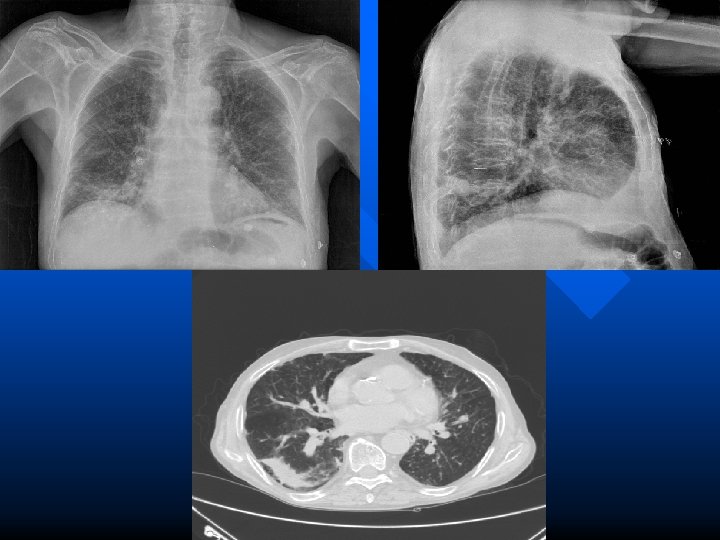

Broncopolmonite sup. dx. Rx normale dopo terapia

Broncopolmonite da Mycoplasma

Broncopolmonite da Chlamidia